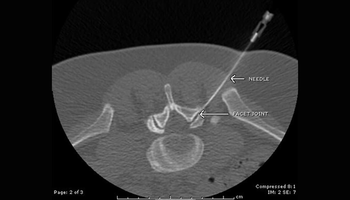

Infiltrations rachidiennes sous contrôle scanner